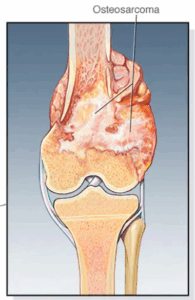

Cancer bone

Bone cancer is a growth of cells that starts in a bone. Bone cancer can start in any bone. But it most often affects the thighbone.